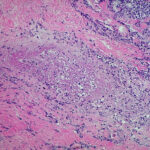

Histopathology . Pyoderma gangrenosum exhibits a dichotomous tissue reaction, showing central necrotizing suppurative inflammation, usually with ulceration, and a peripheral lymphocytic vascular reaction comprising perivascular and intramural lymphocytic infiltrates, usually without fibrin deposition or mural necrosis . Transitional areas show neutrophils in a loose cuff around the angiocentric lymphocytic infiltrates, defining a mixed lymphocytic and neutrophilic vascular reaction termed a Sweet’s-Iike vascular reaction . Bullous lesions may also demonstrate a Sweet’s-like vascular reaction with perivascular disintegrating neutrophilic infiltrates and hemorrhage without mural necrosis or luminal fibrin deposition. At variance with Sweet’s syndrome is destruction of the connective tissue framework with resultant tissue pathergy . Although a leukocytoclastic vasculitis may be observed in areas of maximal tissue pathology, pyoderma gangrenosum does not reflect a primary vasculitis . In some cases a necrotizing pustular follicular reaction may be the central nidus of the lesion, particularly in the vesicular pustular variant associated with ulcerative colitis or hepatobiliary disease. In the superficial granulomatous variant, florid pseudoepitheliomatous hyperplasia may be observed along with the intraepithelial and superficial dermal suppurative granulomatous inflammation with admixed plasma cells and eosinophils . Gases of pyoderma gangrenosum associated with Grohn’s disease may have areas of granulomatous inflammation . |